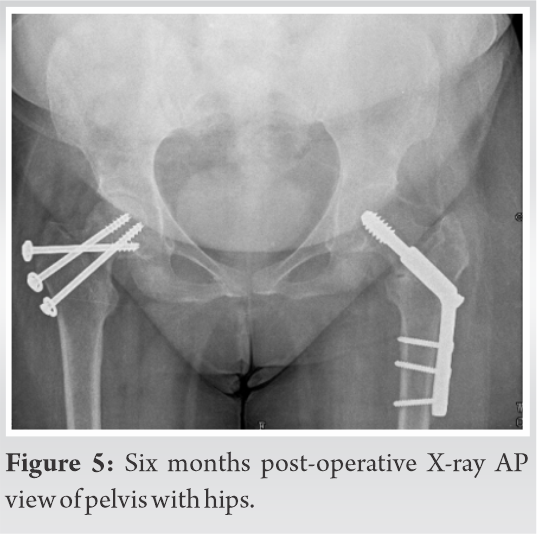

We planned dynamic hip screw for the intertrochanteric fracture and multiple cannulated cancellous screws to stabilize fracture neck of femur in the same sitting. The patient and relatives were prognosticated about the per-operative, post-operative, early, and late complications. In the operation theater with the patient on traction table, we first stabilized the intertrochanteric fracture with dynamic hip screw on the left side. After attempting closed reduction of the displaced femoral neck fracture on the right side, under image intensification, and having achieved it, it was fixed with three 6.5 mm cannulated cancellous screws, one of them as derotation screw. The per-operative period was uneventful. For next 48 h, she was kept in high dependency unit for monitoring after which she was shifted to the general orthopedic ward. Check X-ray taken on 2nd post-operative day was acceptable (Fig. 2, 3, 4). The same day 1st change of dressing was done. In bed physiotherapy was started with leg hanging and quadriceps exercise. Right shoulder remained immobilized. Patient was discharged with advice to attend OPD for stitch removal on 14th post-operative day. At stitch removal, her surgical wounds were found to be healthy. Patient was advised to carry on physiotherapy and non-weight bearing and was asked to follow-up after 1 month.

As lockdown was enforced from March 23, 2020, in COVID-19 pandemic, restricting mobility and because of fear of contracting COVID, she did not attend OPD. Telephonic conversation was done to know her condition and it was found satisfactory. Patient physically reported at the end of 3rd month. X-ray of pelvis with both hips was taken which showed well-advanced stage of union. We wanted her to start weight bearing on the left lower limb (and no weight bearing on right lower limb) but she was apprehensive to use crutches because of post-injury discomfort in right shoulder. She started this in 4th month as per telephonic conversation. After 6 months from the surgery, she was readmitted in our hospital under the nephrology unit with reduced hemoglobin. She was treated and two units of packed cell were transfused. Her X-ray showed fractures well united (Fig. 5) and she could walk without support. She was asked to follow-up at 3 months interval. At last follow-up of 9 months her X-ray showed well united fracture in both AP and lateral view (Fig. 6a, b, c) and she had good range of movement in both hips.